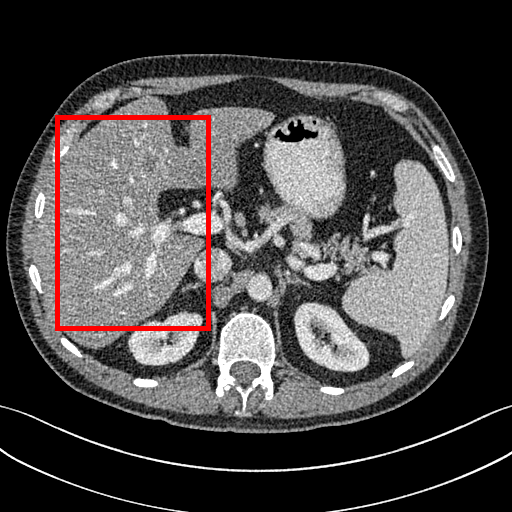

To demonstrate the effectiveness of the proposed network, we perform the qualitative comparisons over three representative abdominal images presented in Figs. 3, 5 and 7. For better evaluations of the image quality with different denoising models, zoomed regions-of-interest (ROIs) are marked by red rectangles and shown in Figs. 4, 6 and 8 respectively. Note that all results from different denoising models focus on two aspects: content restoration and noise-reduction. All CT images in axial view are displayed in the angiography window [-160, 240]HU.

The real NDCT images and corresponding LDCT images are presented in Figs. 3a and 3b. As observed, there are distinctions between ground truth (NDCT) images and LDCT images. Figs. 3a and 7a show the lesions/metastasis. Fig. 5a presents focal fatty sparing/focal fat. In Figs. 4a, 6a and 8a, these lesions can be clearly observed in NDCT images; in contrast, from Figs. 4b, 6b, and 8b, it can be seen that the original LDCT image is noisy, and lacks structural features for task-based clinical diagnosis. All adopted denoising models suppress noise to some extent.

Mean-based methods can effectively reduce noise, but the side effect is impaired image contents. In Fig. 3c, -net greatly suppresses the noise, but blurs some crucial structural information in the porta hepatis region. Meanwhile, some waxy artifacts can still be observed in Fig. 6c. -net does not produce good visual quality because it assumes that the noise is independent of local characteristics of the images. Even though it retains high SNR, its results are not clinically preferable. Compared with -net, in Figs. 3d and 5d, it can been seen that -net encourages less blurring and preserves more structural information. However, as observed in Fig. 4d, it still over-smooths some anatomical details. Meanwhile, in Fig. 6d, there are some blocky effects marked by the blue arrow. The results obtained by RED-CNN [35] deliver high SNR but blur the vessel details as shown in Figs. 4i and 6i.

For SL-based methods, as observed in Figs. 3e and 5e, SL-net generates images with higher contrast resolution and preserves texture of real NDCT images better than -net and -net. However, Figs. 4e and 6e show that SL-net does not preserve the structural features well, and there still remain small streak artifacts. Subsequently, in Figs. 4e and 4f, SL-net and MSL-net have low frequency image intensity variance because SSIM/MS-SSIM is insensitive to uniform biases [49, 51]. On the other hand, -net preserves the overall image intensity, but it does not preserve high contrast resolution well as SL-net and MSL-net do.

To evaluate the effectiveness of our proposed objective function, we compare our method with existing WGAN-based networks, including WGAN and WGAN-VGG. Considering the importance of clinical image quality and specific structural features for medical diagnosis, we adopted the adversarial learning method [41, 42] in our experiments because WGAN could help to capture more structural information. Nevertheless, based on our prior experience, utilizing WGAN alone may yield stronger noise than other selected approaches, because it only maps the data distribution from LDCT to NDCT without consideration of local voxel intensity and structural correlations. The observations demonstrate that the noise texture is coarse in the images, as shown in Fig. 4g and Fig. 8g, which support our intuition.

Indeed, the images of WGAN-VGG[37], as shown in Fig. 3j, exhibit better visual quality with respect to more details and share structural details similar to NDCT images according to human perceptual evaluations. However, Figs. 4j (marked by the red circle) and 6j (marked by the green circle) suggest that it may severely distort the original structural information. A possible reason is that the VGG network [47] is a pre-trained deep CNN network based on natural images, and the structural information and contents of natural images are different from medical images.

Compared with WGAN and WGAN-VGG, our proposed SMGAN-3D, as shown in Figs. 4l (marked by the red circle) and 6l (marked by the green circle), can more clearly visualize the metastasis and better preserve of the portal vein.

To validate the robustness of DL-based methods, we compared our method with the image space denoising method. Figs. 4h and 6h show that BM3D blurs the low-contrast lesion marked by the red circle and smooths specific features marked by the blue arrow. In contrast, SMGAN-3D exhibits better on the low-contrast lesion and yields sharper features as shown in Figs. 4l and 6l.